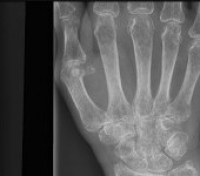

Cientistas da Nasa acreditam ter encontrado uma maneira de diagnosticar osteoporose em seus estágios iniciais.

Atualmente, a doença pode passar despercebida durante anos e muitas vezes só é diagnosticada em exames realizados depois que o enfraquecimento dos ossos levou a uma fratura.

O equilíbrio ou a abundância desses diferentes isótopos quando o osso é fraturado ou formado pode indicar alterações na densidade óssea nos seus estágios iniciais.

A técnica permite detectar a perda de massa óssea após uma semana de repouso – muito antes, portanto, de mudanças na densidade óssea terem sido detectadas por escaneamentos convencionais.